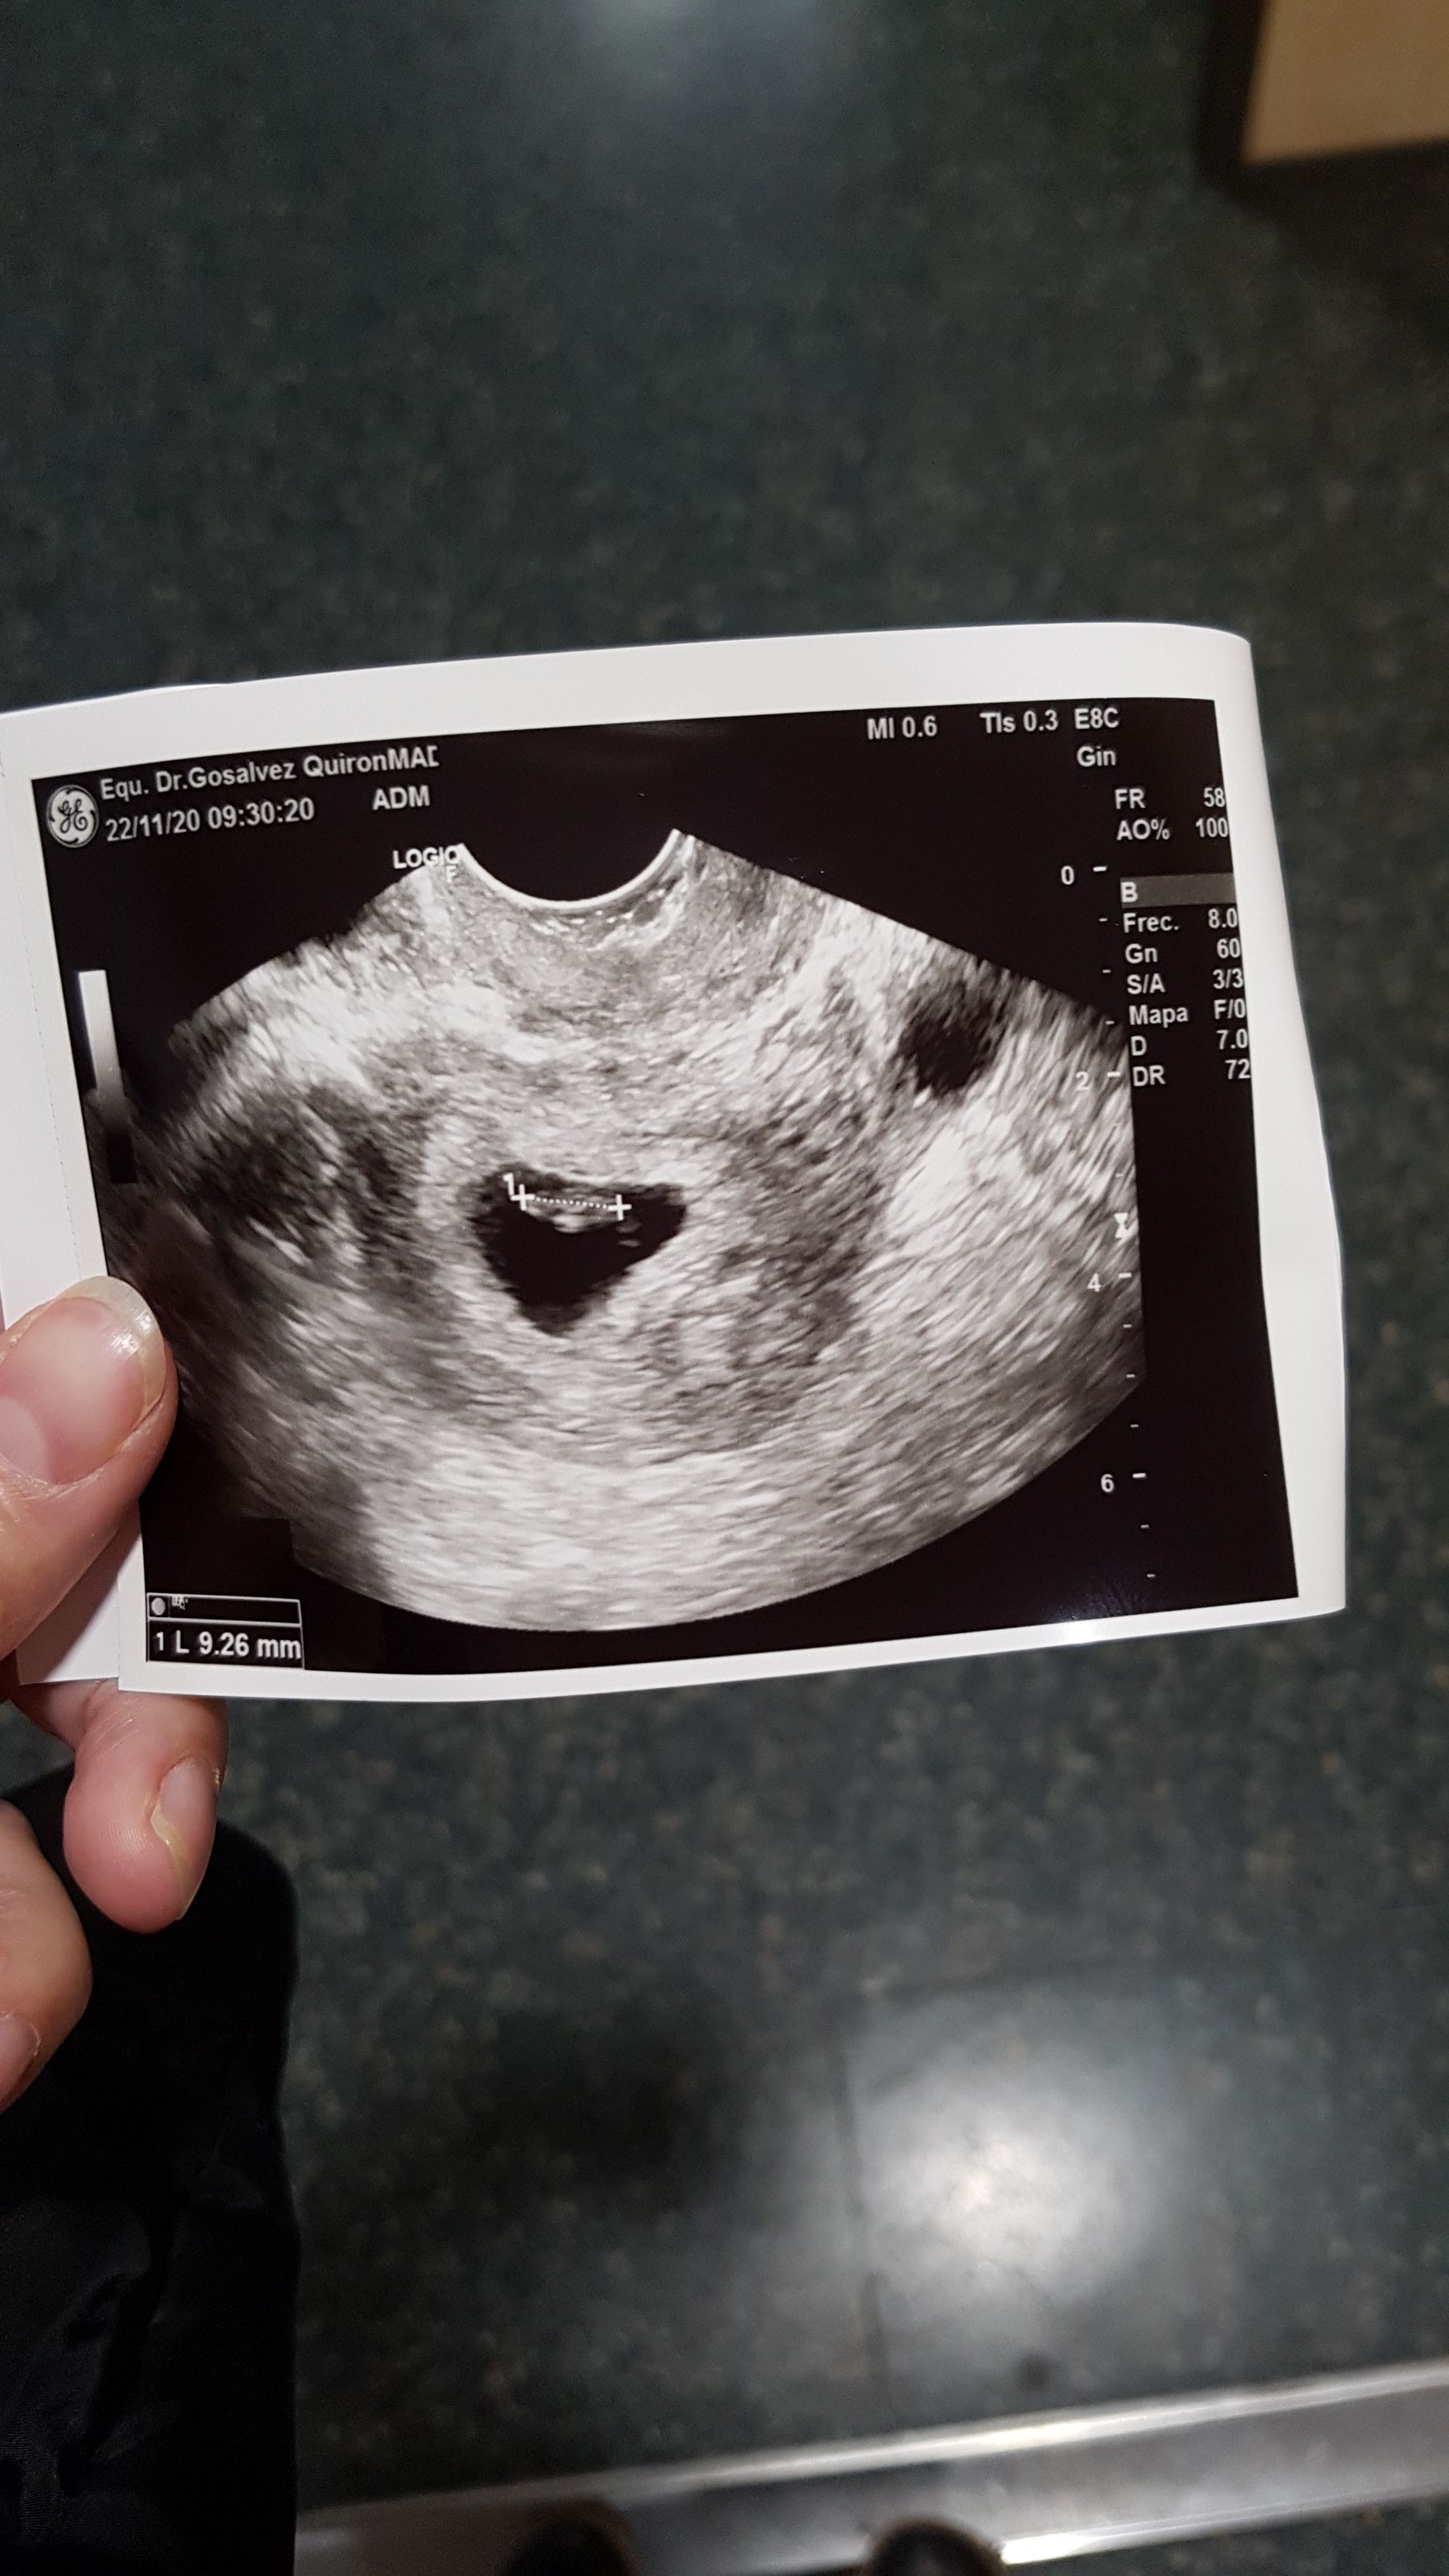

Ja dziś zaliczyłam klinikę bo od wczoraj krwawiłam nieco ....

I lekarz kazał mi przyjechać dla świętego spokoju ....

To tylko jakieś naczynko czy zadrapanie na szczęście. W 3 dni urosła 3 mm 😃Zobacz załącznik 1204947